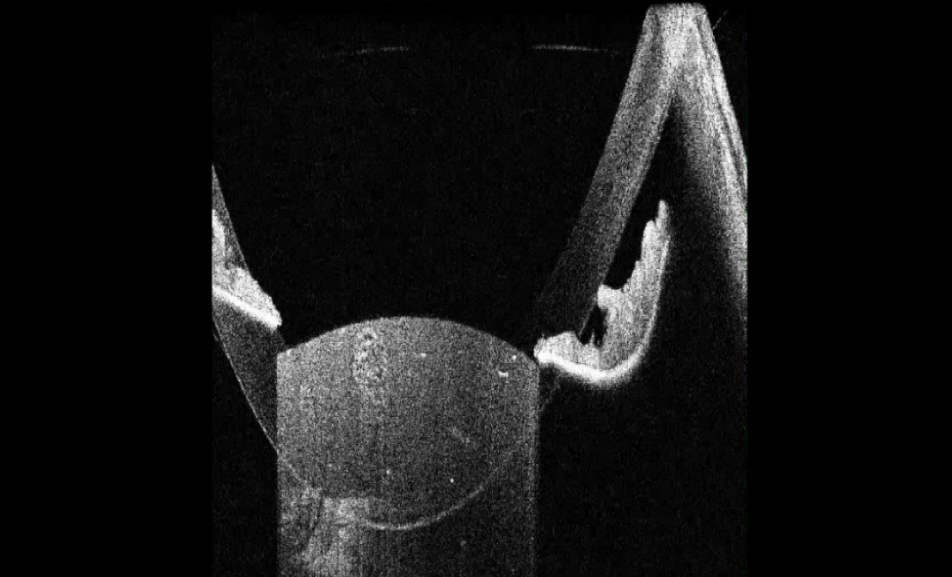

В исследование вошли 196 пациентов (250 глаз) с перезрелой катарактой. Пациенты были разделены на 2 группы (по 125 глаз в каждой группе). Всем пациентам интраоперационно с помощью интегрированной в операционный микроскоп И-ОКТ, Hi-R NEO (HAAG STREIT, Германия), определяли тип перезрелой катаракты (рис. 1–4).

Рис. 3. Тип 3 перезрелой катаракты: выпуклая передняя капсула хрусталика, гиперрефлективные полосы набухших кортикальных волокон, внутрихрусталиковые щели, области однородного вида «матового стекла»